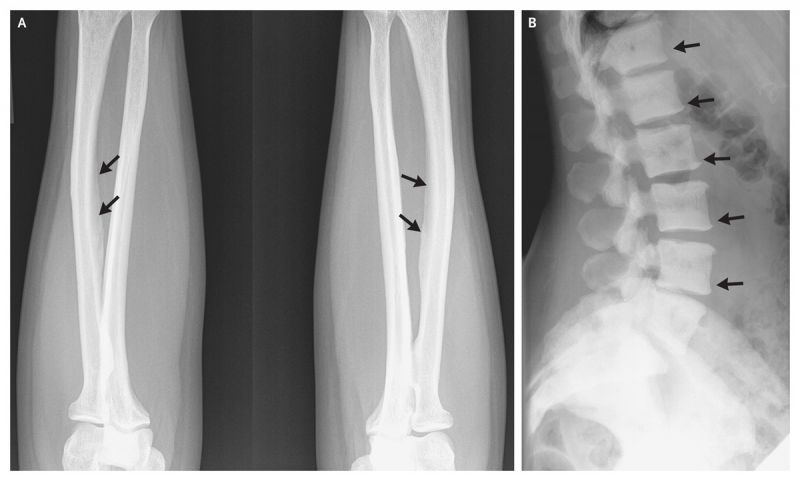

ਇਸ ਜਾਂਚ 'ਚ ਕਿਹਾ ਗਿਆ ਹੈ ਕਿ ਜ਼ਿਆਦਾ ਮਾਤਰਾ 'ਚ ਫ਼ਲੋਰਾਇਡ ਸਰੀਰ 'ਚ ਪੁੱਜਣ ਨਾਲ ਸਕੈਲੇਟਸ ਫ਼ਲੂਰੋਸਿਸ ਦੀ ਸੰਦੇਹ ਰਹਿੰਦੀ ਹੈ। ਇਸ 'ਚ ਜੋੜਾਂ 'ਚ ਕੈਲਸ਼ੀਅਮ ਜਮਣ ਲੱਗਦਾ ਹੈ ਉਹ ਅਕੜ ਜਾਂਦੇ ਹਨ।

ਸੰਸਾਰ ਸਿਹਤ ਸੰਗਠਨ ਨੇ ਵੀ ਨਿੱਤ ਛੇ ਮਿਲੀਗਰਾਮ ਤੋਂ ਜ਼ਿਆਦਾ ਮਾਤਰਾ 'ਚ ਫ਼ਲੋਰਾਈਡ ਸਰੀਰ 'ਚ ਪੁੱਜਣ 'ਤੇ ਸਕੈਲੇਟਸ ਫ਼ਲੂਰੋਸਿਸ ਹੋਣ ਦੀ ਸੰਦੇਹ ਜਤਾਈ ਹੈ। ਇਸ ਹਿਸਾਬ ਨਾਲ ਦੇਖਿਆ ਜਾਵੇ ਤਾਂ ਇਕ ਦਿਨ 'ਚ ਚਾਰ ਕਪ ਤੋਂ ਜ਼ਿਆਦਾ ਚਾਹ ਪੀਣਾ ਸਿਹਤ ਲਈ ਖ਼ਤਰਨਾਕ ਹੋ ਸਕਦਾ ਹੈ।